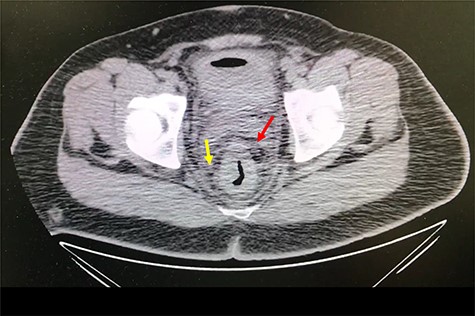

A 32-year-old man with no past medical or surgical history presented to the emergency department (ED) in April 2018, distressed and complaining of worsening pneumaturia for the past 3 days. The patient reported a 2-week history of polyuria, dysuria, suprapubic pain, tenesmus and inability to control his sphincters, prior to the ED-onset presentation. Further history revealed a 50-pound involuntary weight loss in a 5-month period, with partially treated urinary tract infections without resolution. He denied toxic habits, high-risk sexual behavior nor family history for colorectal cancer or inflammatory bowel disease. Based on the symptoms described, the rare triad of Gouverneur’s syndrome related to the EVF was considered. Physical evaluation revealed no palpable anorectal masses, adequate rectal tone and no visible gross blood. Urine analysis showed pyuria, hematuria, proteinuria with urine culture positive for Escherichia coli. Abdominopelvic computed tomography (CT) scan showed circumferential wall thickening of the rectum with surrounding fat stranding and numerous prominent pelvic lymph nodes (Fig. 1). Additionally, the scan showed pericolonic gas and fluid collection with a fistulous tract adjacent to the proximal rectum and the bladder (Fig. 2). In Figure 3, two hepatic hypodense lesions located in the right lobe of the liver were identified suggestive of metastasis. During colonoscopy, at approximately 20 cm from the anal verge a large, firm, irregular, friable, concentric mass was identified obstructing 95% of the lumen (Fig. 4). During surgery, the mass was not amenable for resection, due to its low pelvic location and size; a loop colostomy was performed for decompression, with liver tru-cut needle biopsy. Intraoperative cystoscopy was unsuccessful in placement of ureteral stents due to tumor invasion to the bladder.

Axial abdomen and pelvis CT scan showing fistulous tract adjacent to the proximal rectum and the bladder (red arrow) and enlarged lymph nodes (yellow arrow).